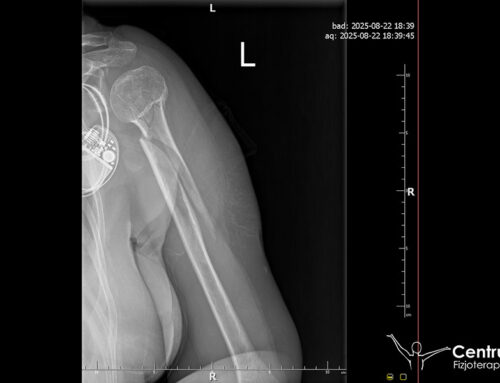

Uszkodzenia rogu przedniego łąkotki bocznej widać najlepiej na rezonansie magnetycznym. Można wówczas nie tylko określić wielkość uszkodzenia, ale również po części jego rodzaj. Oczywiście wszystkie szczegóły dotyczące danego uszkodzenia uwidacznia się w pełni precyzyjnie dopiero podczas zabiegu, gdy lekarz chirurg ortopeda wejdzie artroskopem do stawu kolanowego. USG nie jest polecane w diagnostyce uszkodzeń łąkotek.